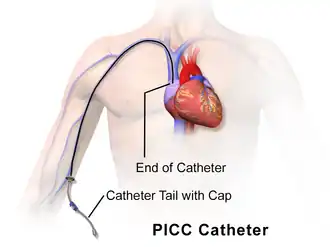

Een PICC-lijn (uitgesproken als "piklijn") is een buigzaam dun infuusslangetje dat in een ader van de menselijke bovenarm geplaatst wordt.[2] Het uiteinde van deze lijn komt boven het hart uit in de grote holle ader in de borstkas. PICC is de afkorting van peripherally inserted central catheter, perifeer (dus aan de buitenzijde) ingebrachte centraal veneuze katheter. Een PICC-lijn wordt door een bevoegde anesthesist, radioloog, chirurg of speciaal opgeleide verpleegkundige bij een patiënt ingebracht die langdurig via een infuus in de bloedbaan geneesmiddelen of voeding toegediend moet krijgen of bij wie vaak bloed moet worden afgenomen.

De PICC-lijn wordt in een ader in de arm aan de binnenbovenkant van de elleboog ingebracht bij een liggende patiënt: in de vena basilica (koningsader), de vena cephalica of de vena brachialis (brachiale ader). Er moet al eerder met bloedverdunners gestopt zijn. Met echoscopie wordt de loop van de aders in de arm (meestal de rechterarm) bekeken. Als de aders in de rechterarm ongeschikt zijn (bijvoorbeeld omdat ze te dun zijn) wordt voor de linkerarm gekozen. Afhankelijk van het soort slangetje kan het na meting met een rolmaat langs de patiënt op de goede lengte worden afgeknipt. Onder plaatselijke verdoving en in zo steriel mogelijke omstandigheden wordt dan de PICC-lijn na voorbereiding met een tijdelijke voerdraad (hulplijn) echogeleid ingebracht en doorgeschoven. De pleister op de ingang voor de PICC-lijn in de huid heeft een plastic schildje (Statlock of eerst een eenmalige Securacath) om het slangetje langdurig te fixeren en wordt wekelijks vervangen. De ingang van de slang die uit de arm steekt kan bijvoorbeeld aan een buisje van een infuuszak worden vastgeschroefd en worden afgesloten met een afsluitventiel (bionecteur, microvalve).[3]